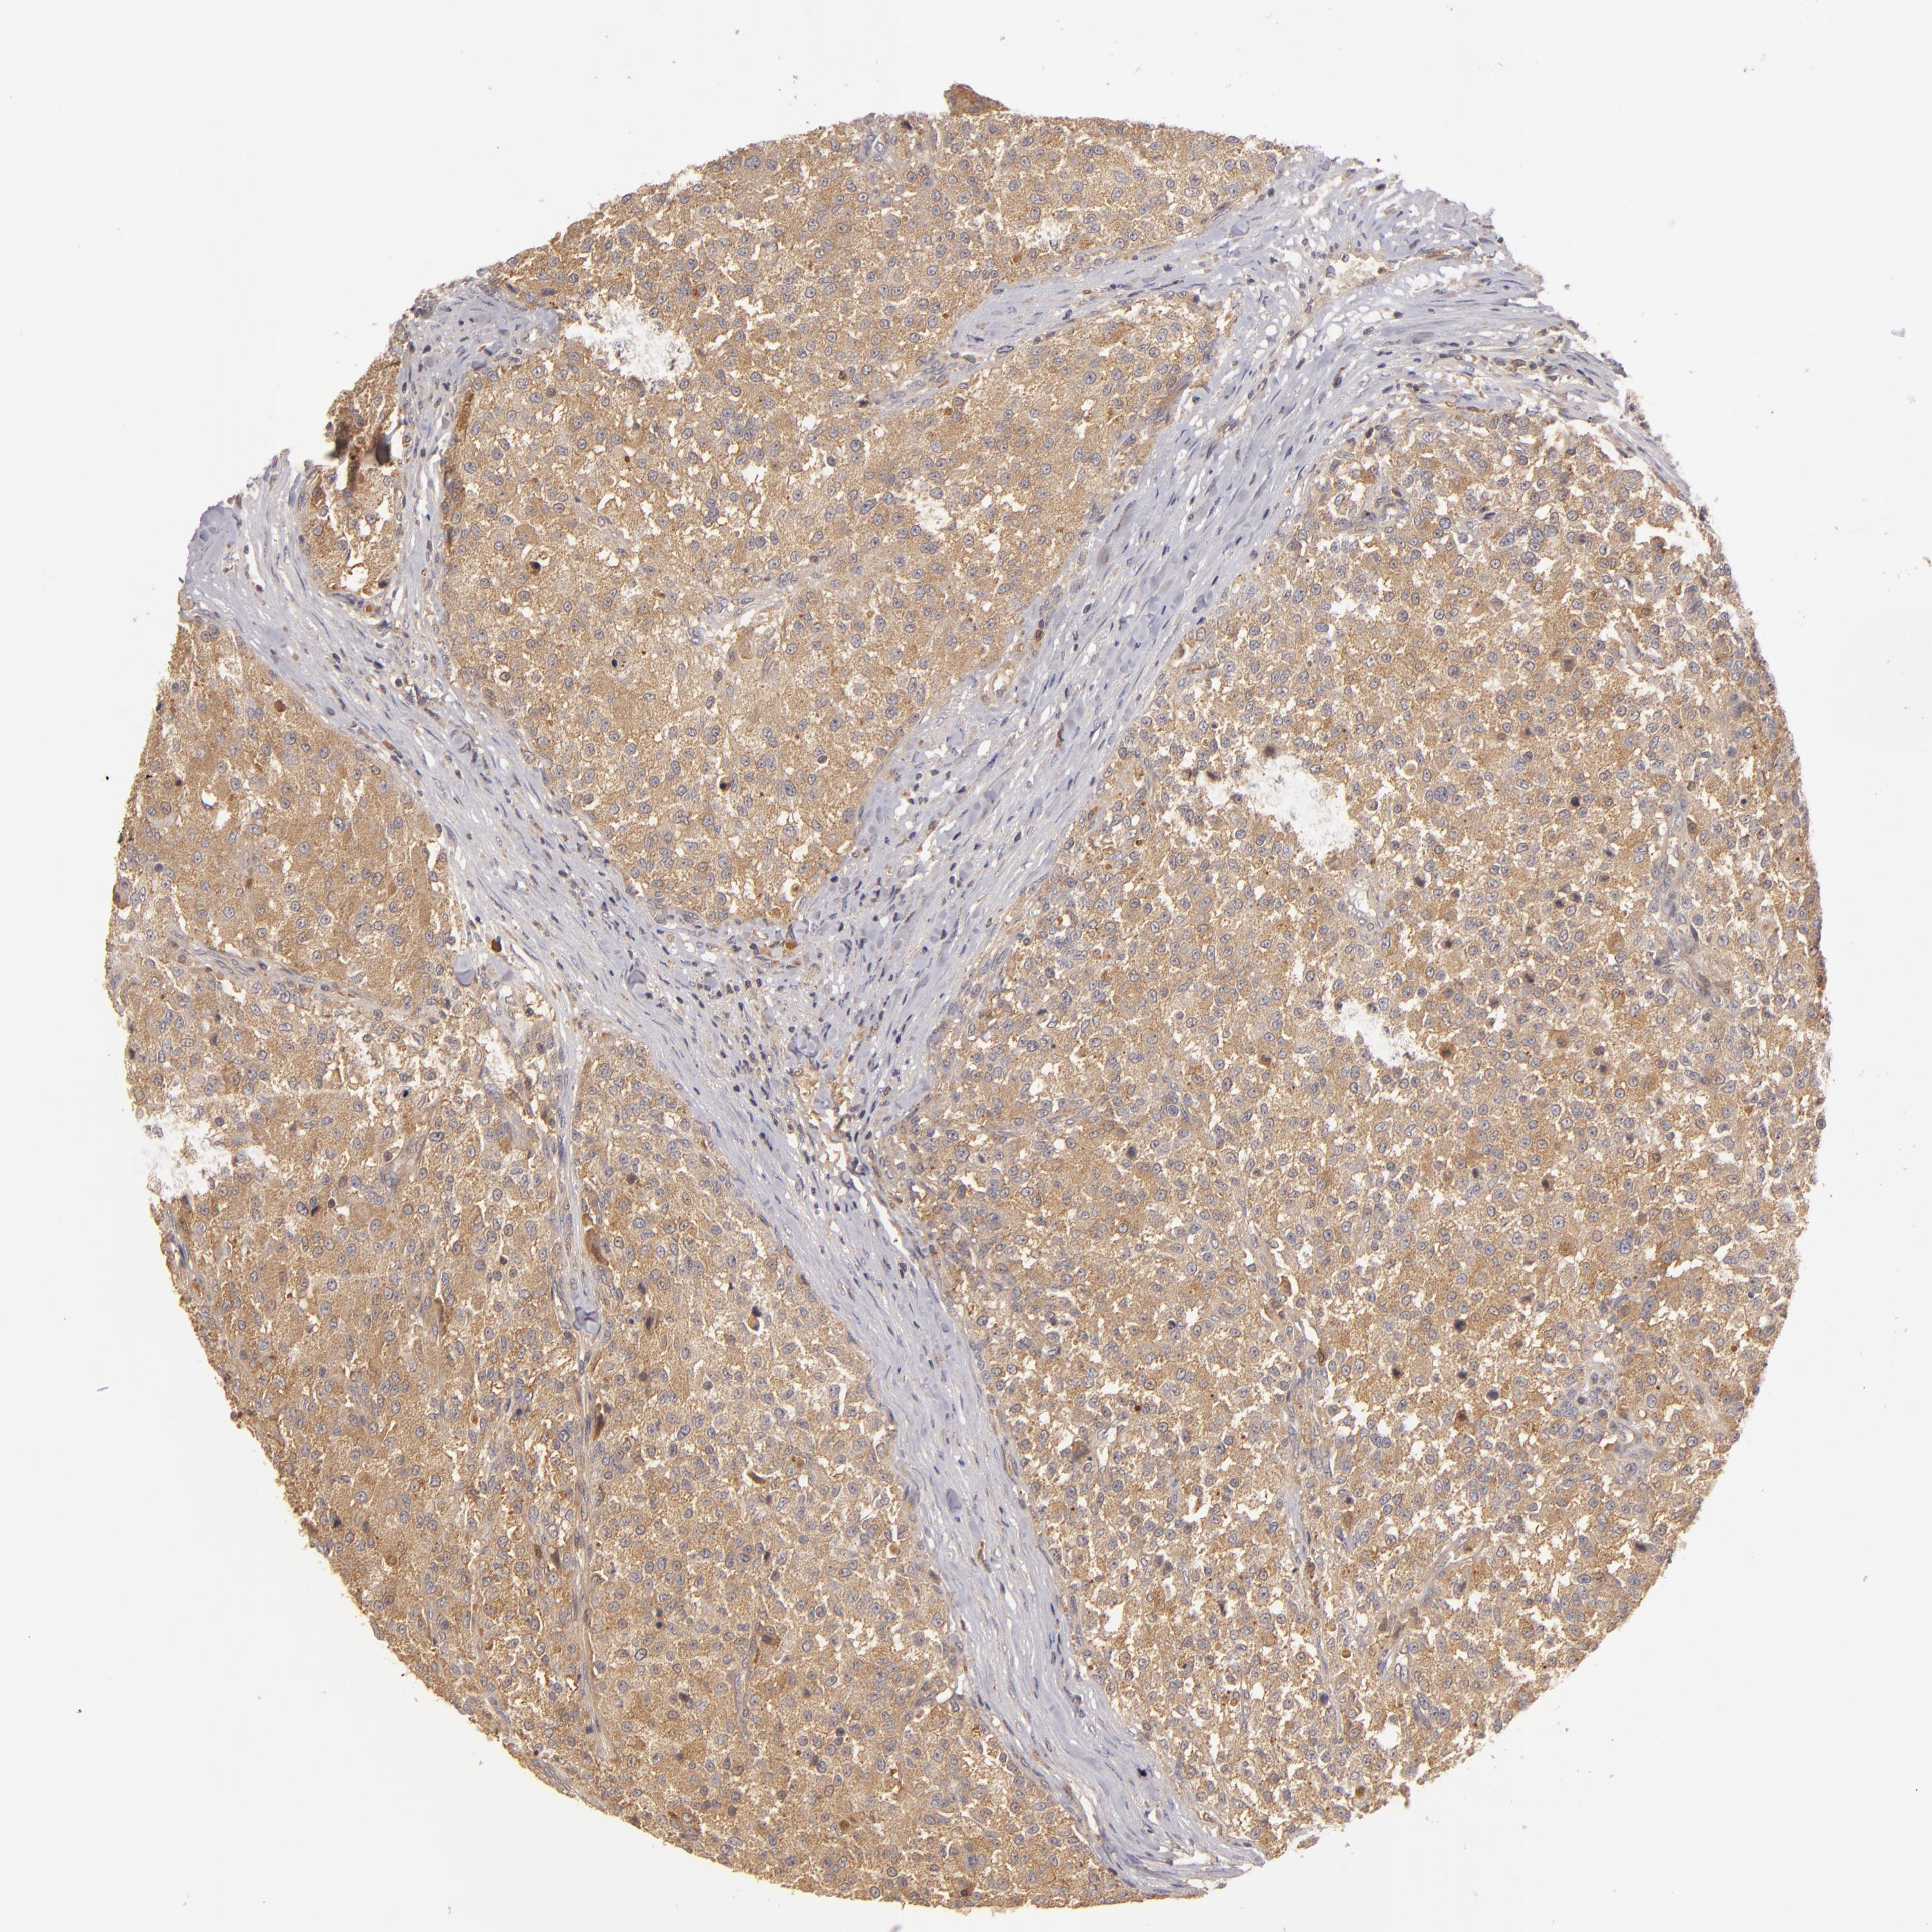

TESTIS CANCER - Protein expressioni

A mouse-over function shows sample information and annotation data. Click on an image to view it in a full screen mode. Samples can be filtered based on level of antibody staining by selecting one or several of the following categories: high, medium, low and not detected. The assay and annotation is described here.

Note that samples used for immunohistochemistry by the Human Protein Atlas do not correspond to samples in the TCGA dataset.

Antibody stainingi

Antibody staining in the annotated cell types in the current human tissue is reported as not detected, low, medium, or high, based on conventional immunohistochemistry profiling in selected tissues. This score is based on the combination of the staining intensity and fraction of stained cells.

Each image is clickable and will lead to virtual microscopy that enables deeper exploration of all samples and also displays staining intensity scores, fraction scores and subcellular localization as well as patient and tissue information for each sample.

Antibody HPA001890

Antibody CAB010469

Antibody CAB013225

Carcinoma, Embryonal, NOS

Seminoma, NOS